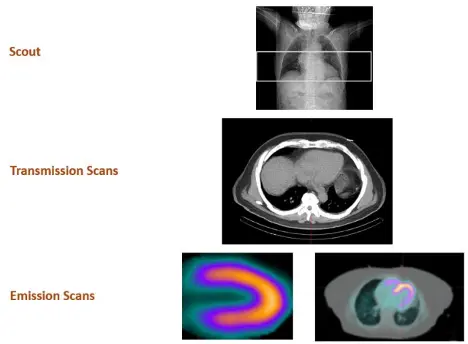

tl;dr: We collect transmission and perfusion images and superimpose them on one another. The CT and perfusion contours of the heart should be properly aligned (co-registration).

- Scout image to localize the heart

- Transmission scans – most commonly done with low-dose CT AC

- 📝 AC is a must for PET, but optional for SPECT

- 3 approaches to do AC, but everyone does CT-AC these days as it is very fast (patient motion is less of an issue), lower energy, and low noise/higher resolution

- Emission scans

- Patient is

-1753742157382.webp)